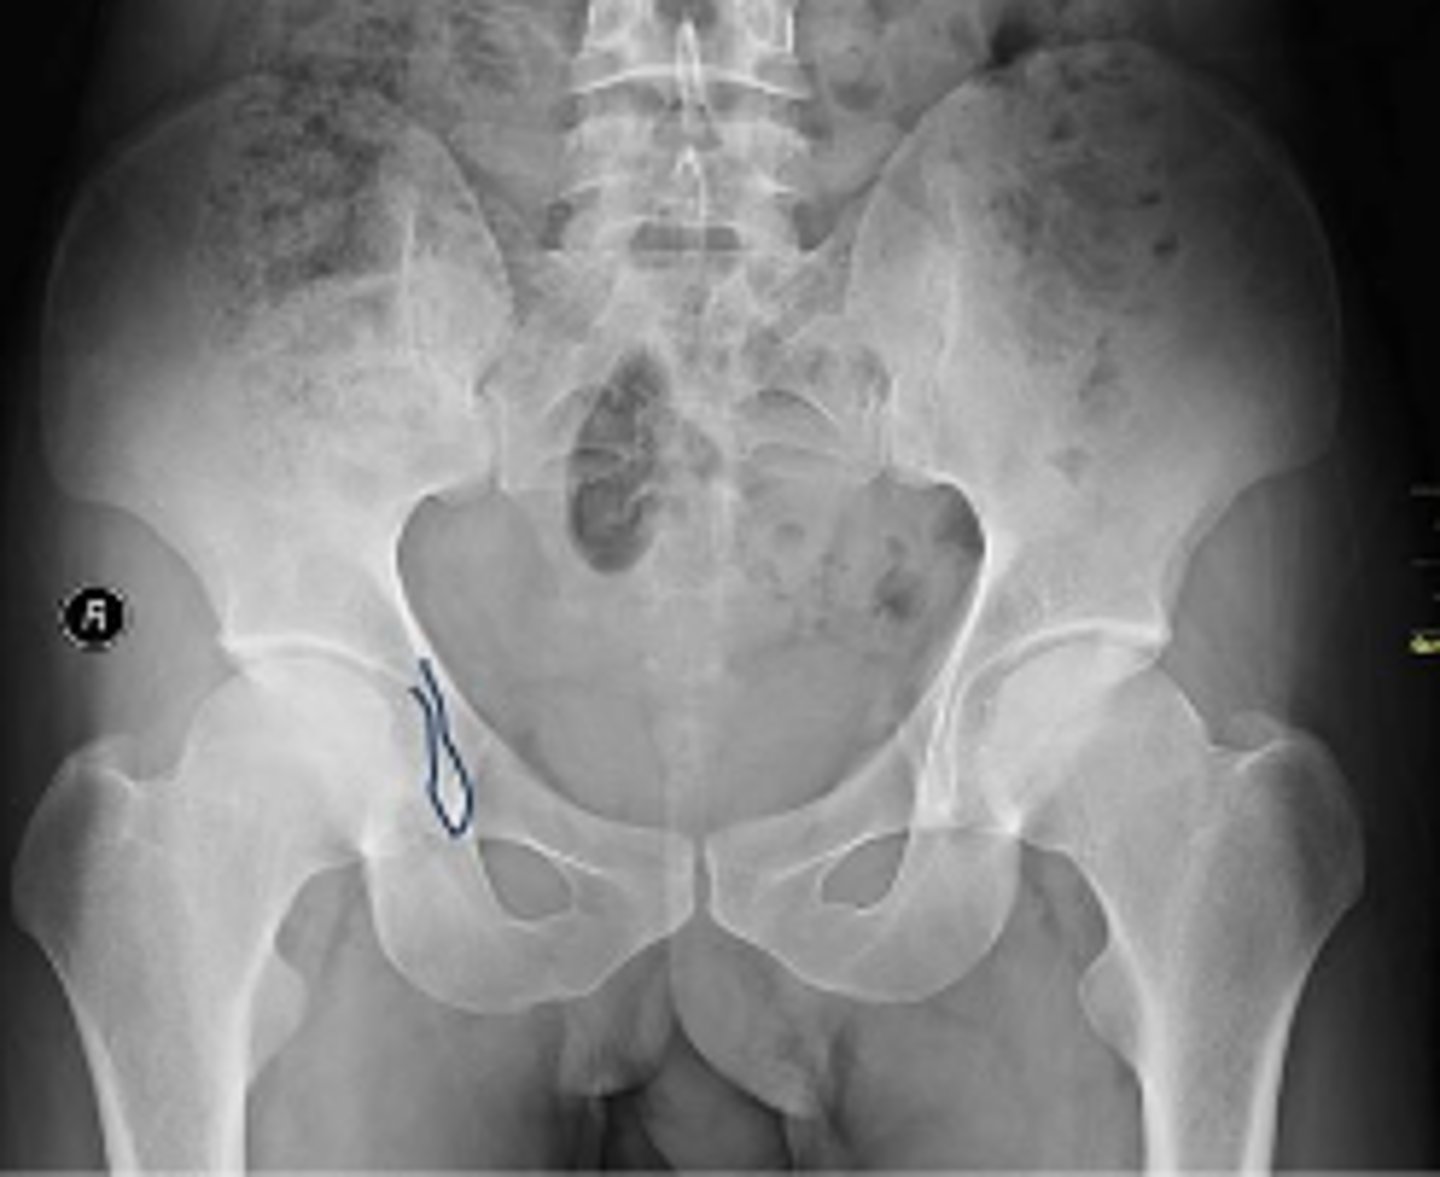

AP pelvis or bilateral hips

What is the name of the radiographic view?

What is outlined?

Right sacroiliac joint

Pubic symphysis

What joint space is the arrow pointing to?